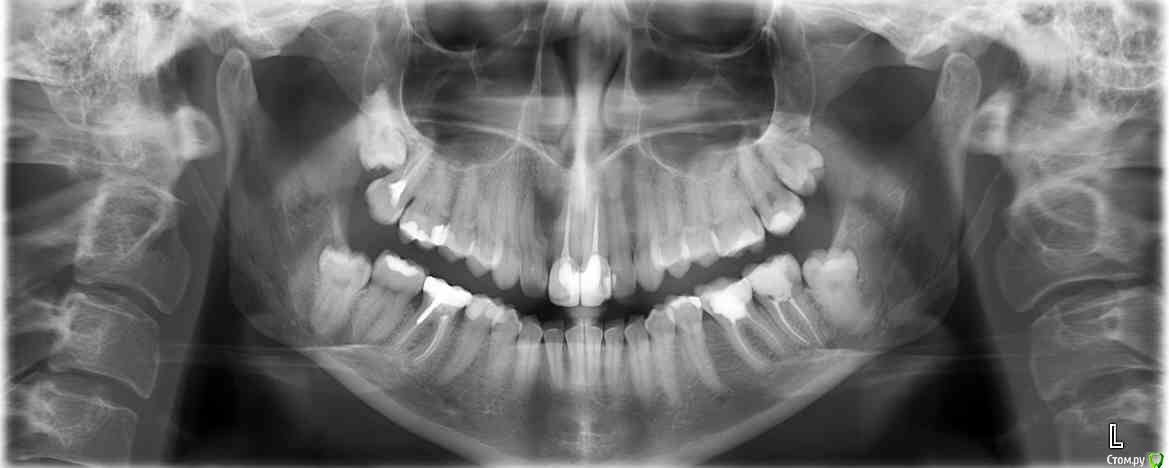

olga1985 Опубликовано 19 февраля, 2016 Поделиться Опубликовано 19 февраля, 2016 Добрый день, Перед удалением зубов мудрости врач сделал снимки и обнаружил большую кисту на верхнем переднем втором зубе. Сказал, только удалению подлежит и что вылечить невозможно. Киста очень большая, разьела кость и возможно нужно будет удалять и соседний передний зуб. Я живу за границей и обратилась за консультаций к местному стоматологу. Он обнаружил у меня аномалию зуба: "зуб в зубе" и что один из зубов умер, а второй корень живой и поэтому кажется что зуб живой. Второй мертвый канал непроходимый, и его запломбировать нельзя. Сказал, что вылечить можно резекцией, но это стоит очень дорого и перпспективы неясны. И что возможно он высверлит больше еще кости чтобы удалить корень, а потом ставить имплант не на что будет. Сказал, лучше сразу имплант. Другой врач за границей сказал - можно резекцию, все будет все хорошо. Про имплант сразу даже не разговаривал. Сказал, можно сохранить зуб. Зуб не болит. Свищ появился после того, как я лет 10 назад ударила десну зубной щеткой когда чистила зубы. И раз в год появляется. Подскажите, пожалуйста, возможно ли созранить зуб с моей аномалией? Заранее спасибо!! Ссылка на комментарий

___49___ Опубликовано 23 февраля, 2016 Поделиться Опубликовано 23 февраля, 2016 (изменено) У вашего зуба 2 канала(а если точно 2 отдельных пульповых камеры, каждая со своим каналом) , зуб аномальный, канал что ближе к центру облитерирован (труднопроходим, или непроходим) , корень со стороны этого канала ближе к кончику частично лизирован(расплавлен) - это он явился причиной возникновения кисты. Киста довольно обширна и частично захватывает соседний центральный резец (не есть хорошо, но пока не критично). Если делать резекцию - необходимо будет пройти трудно проходимый канал и запломбировать его (2ой канал тоже) , сделать в кости окошко , выскоблить всю кисту , обработать корень в полости кисты - все эти мероприятия будут направлены на исключения возможности повторного инфицирования . Преимущества метода при благоприятном исходе: - сохроняем зуб, визуально при улыбке в полости рта у вас ничего не меняется (возможен лишь отек после операции 2-4 дня ) на всех этапах лечения. Недостатки при благоприятном исходе : - Потеря длины корня (в вашем случае я бы не только сошлифовал медиальную стенку виновного зуба с верхушкой , но и срезал бы верхушку соседнего центрального резца на 3 мм), у зуба уменьшится его максимальная функциональная нагрузка ( станет более слабым). При неблагоприятном исходе (вероятность такого 5% в соответствии с литературой) : - потеря зуба, убыль костной ткани, распространение кисты далее (в том числе и с более критичным захватом соседнего зуба) . Соответственно вы встаете перед выбором - либо идете на риск примерно в 5% (что ситуация ухудшится в том числе,для последующей имплантации) и получаете немного более слабые зубы, кость частично (до 80%) восстанавливается, киста уходит, инфекции нет. - либо сразу пресекаете подобный риск, зуб удаляете вместе с инфекцией, имплантируетесь. Изменено 23 февраля, 2016 пользователем ___49___ Ссылка на комментарий